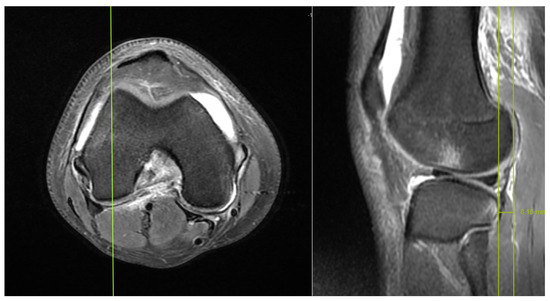

Does Rotation and Anterior Translation Persist as Residual Instability in the Knee after Anterior Cruciate Ligament Reconstruction? (Evaluation of Coronal Lateral Collateral Ligament Sign, Tibial Rotation, and Translation Measurements in Postoperative MRI)

2.1. MRI Evaluation Methods